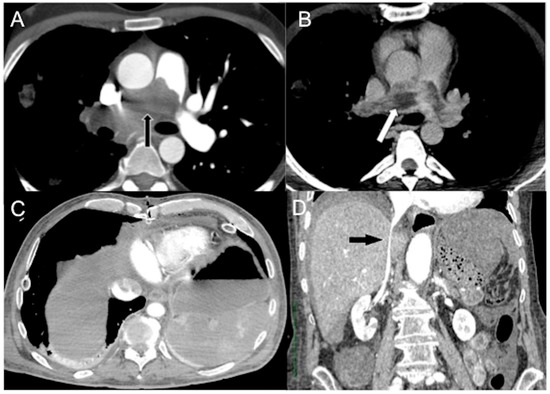

- Focal hot spot sign

Contrast stasis in the right-side cardiac chambers and SVC may result in functional flow of CM through venous collaterals (anterior intercostal, internal thoracic, superior and inferior epigastric veins communicating with paraumbilical vein carrying the blood and the CM to the hepatic vein and to the left lobe of the liver) to the inferior vena cava, generating areas of focally increased blood flow to the liver, typically within segment IV of the left hepatic lobe, known as a focal hot spot sign (Figure 5) [69,70,71].

Figure 5.

CECT axial images in an acutely dyspneic 64-year-old man with SVC obstruction from right lung cancer (not shown) and obstructive shock. Arterial phase (A) shows CM reflux via the larger subcutaneous (green arrow), pericardiophrenic (red arrow) and internal thoracic veins (yellow arrow) to the left hepatic vein (black arrow) generating (B) focal hot spot sign in left liver (black arrow).